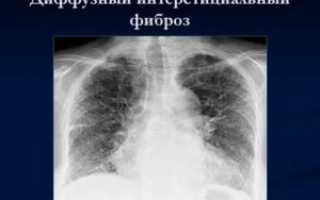

Линейная форма — появляется, как следствие осложнений после перенесенного туберкулеза, пневмонии. Интерстициальный пневмофиброз — при такой форме пациента мучает одышка, заболевание развивается вследствие воспалительных явлений в легочных кровеносных сосудах.

- Диффузный пневмофиброз легких. Самый опасный тип заболевания, который отличается полным или множественными поражениями тканей легких. При этом виде пневмофиброз развивается довольно стремительно. Появляется ярко выраженная дыхательная недостаточность.

Рентгенография является одним из главных методов, помогающим определить наличие различных заболеваний легких. При пневмофиброзе органы дыхания сильно видоизменяются – усиливается и деформируется легочный рисунок, увеличиваются сосудистые тени. Легочные тени со рваными краями, расположенные хаотично, говорят о последних стадиях патологии.

- Диффузный пневмофиброз легких – это наиболее опасная форма заболевания, характеризующаяся множественными поражениями или изменениями всей ткани легкого. Для диффузной формы патологии характерно стремительное прогрессирование, развитие выраженной дыхательной недостаточности. В большинстве случаев состоянию сопутствует развитие плеврофиброза. Плевропневмофиброз легких – это поражение плевры, замещение ее на фиброзную ткань;